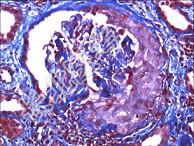

- 多项选择题常见的DM微血管并发症有 ( )

A、糖尿病视网膜病变

B、糖尿病周围神经病变

C、糖尿病肾病

D、腔隙性脑梗死

E、肾动脉硬化